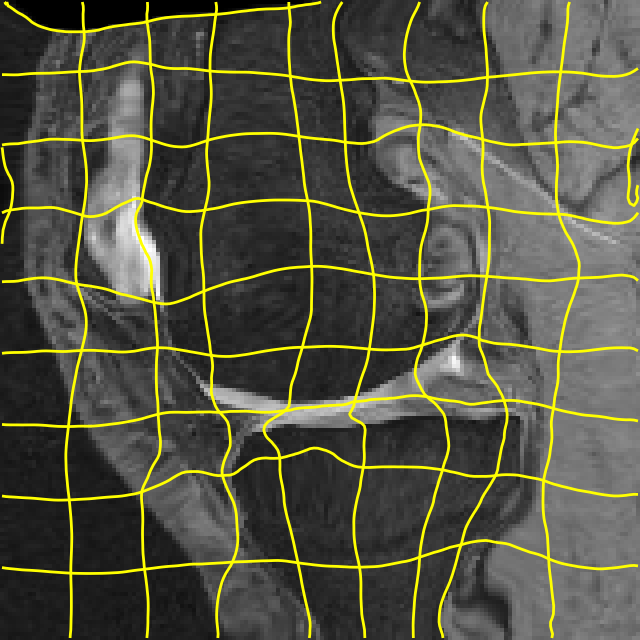

Results: All trained networks are evaluated using Dice overlap scores between predictions and the manual segmentations for the segmentation network, or between the warped moving segmentations and the target segmentations for the registration network. Tabs. 1 and 2 show results for the knee and brain MRI experiments respectively in Dice scores (%). Fig. 2 shows examples of knee MRI registrations and brain MRI segmentations.

Qualitative results: DA achieves more anatomically consistent registrations than the mono-networks on the knee (Fig. 2) and Brain MRI samples (see supplementary material).